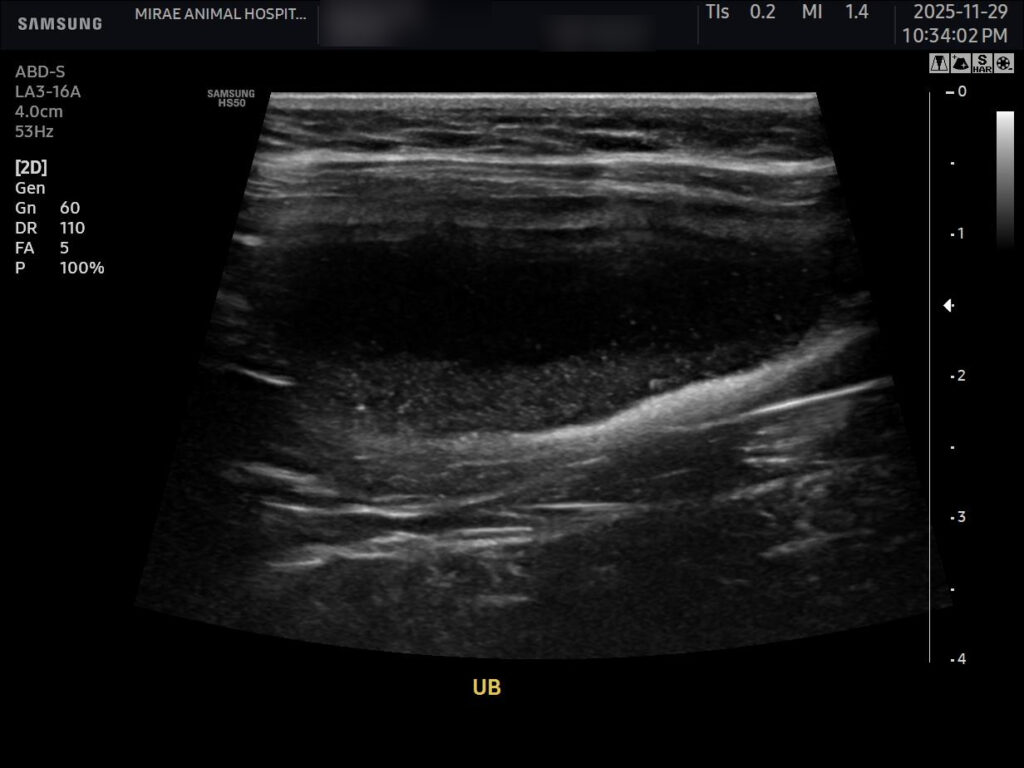

이어 시행한 초음파 검사에서는 방광 내부에 슬러지가 다량 관찰되었고, 중력 방향으로 가라앉아 있는 모습이 뚜렷했습니다. 또한 요도가 확장되어 있었고, 요도 쪽으로도 슬러지가 있는 상태가 확인되었습니다. 다행히 양쪽 신장은 양호한 상태로 확인되었습니다.

환자 초음파 사진/ 출처: 미래동물의료센터